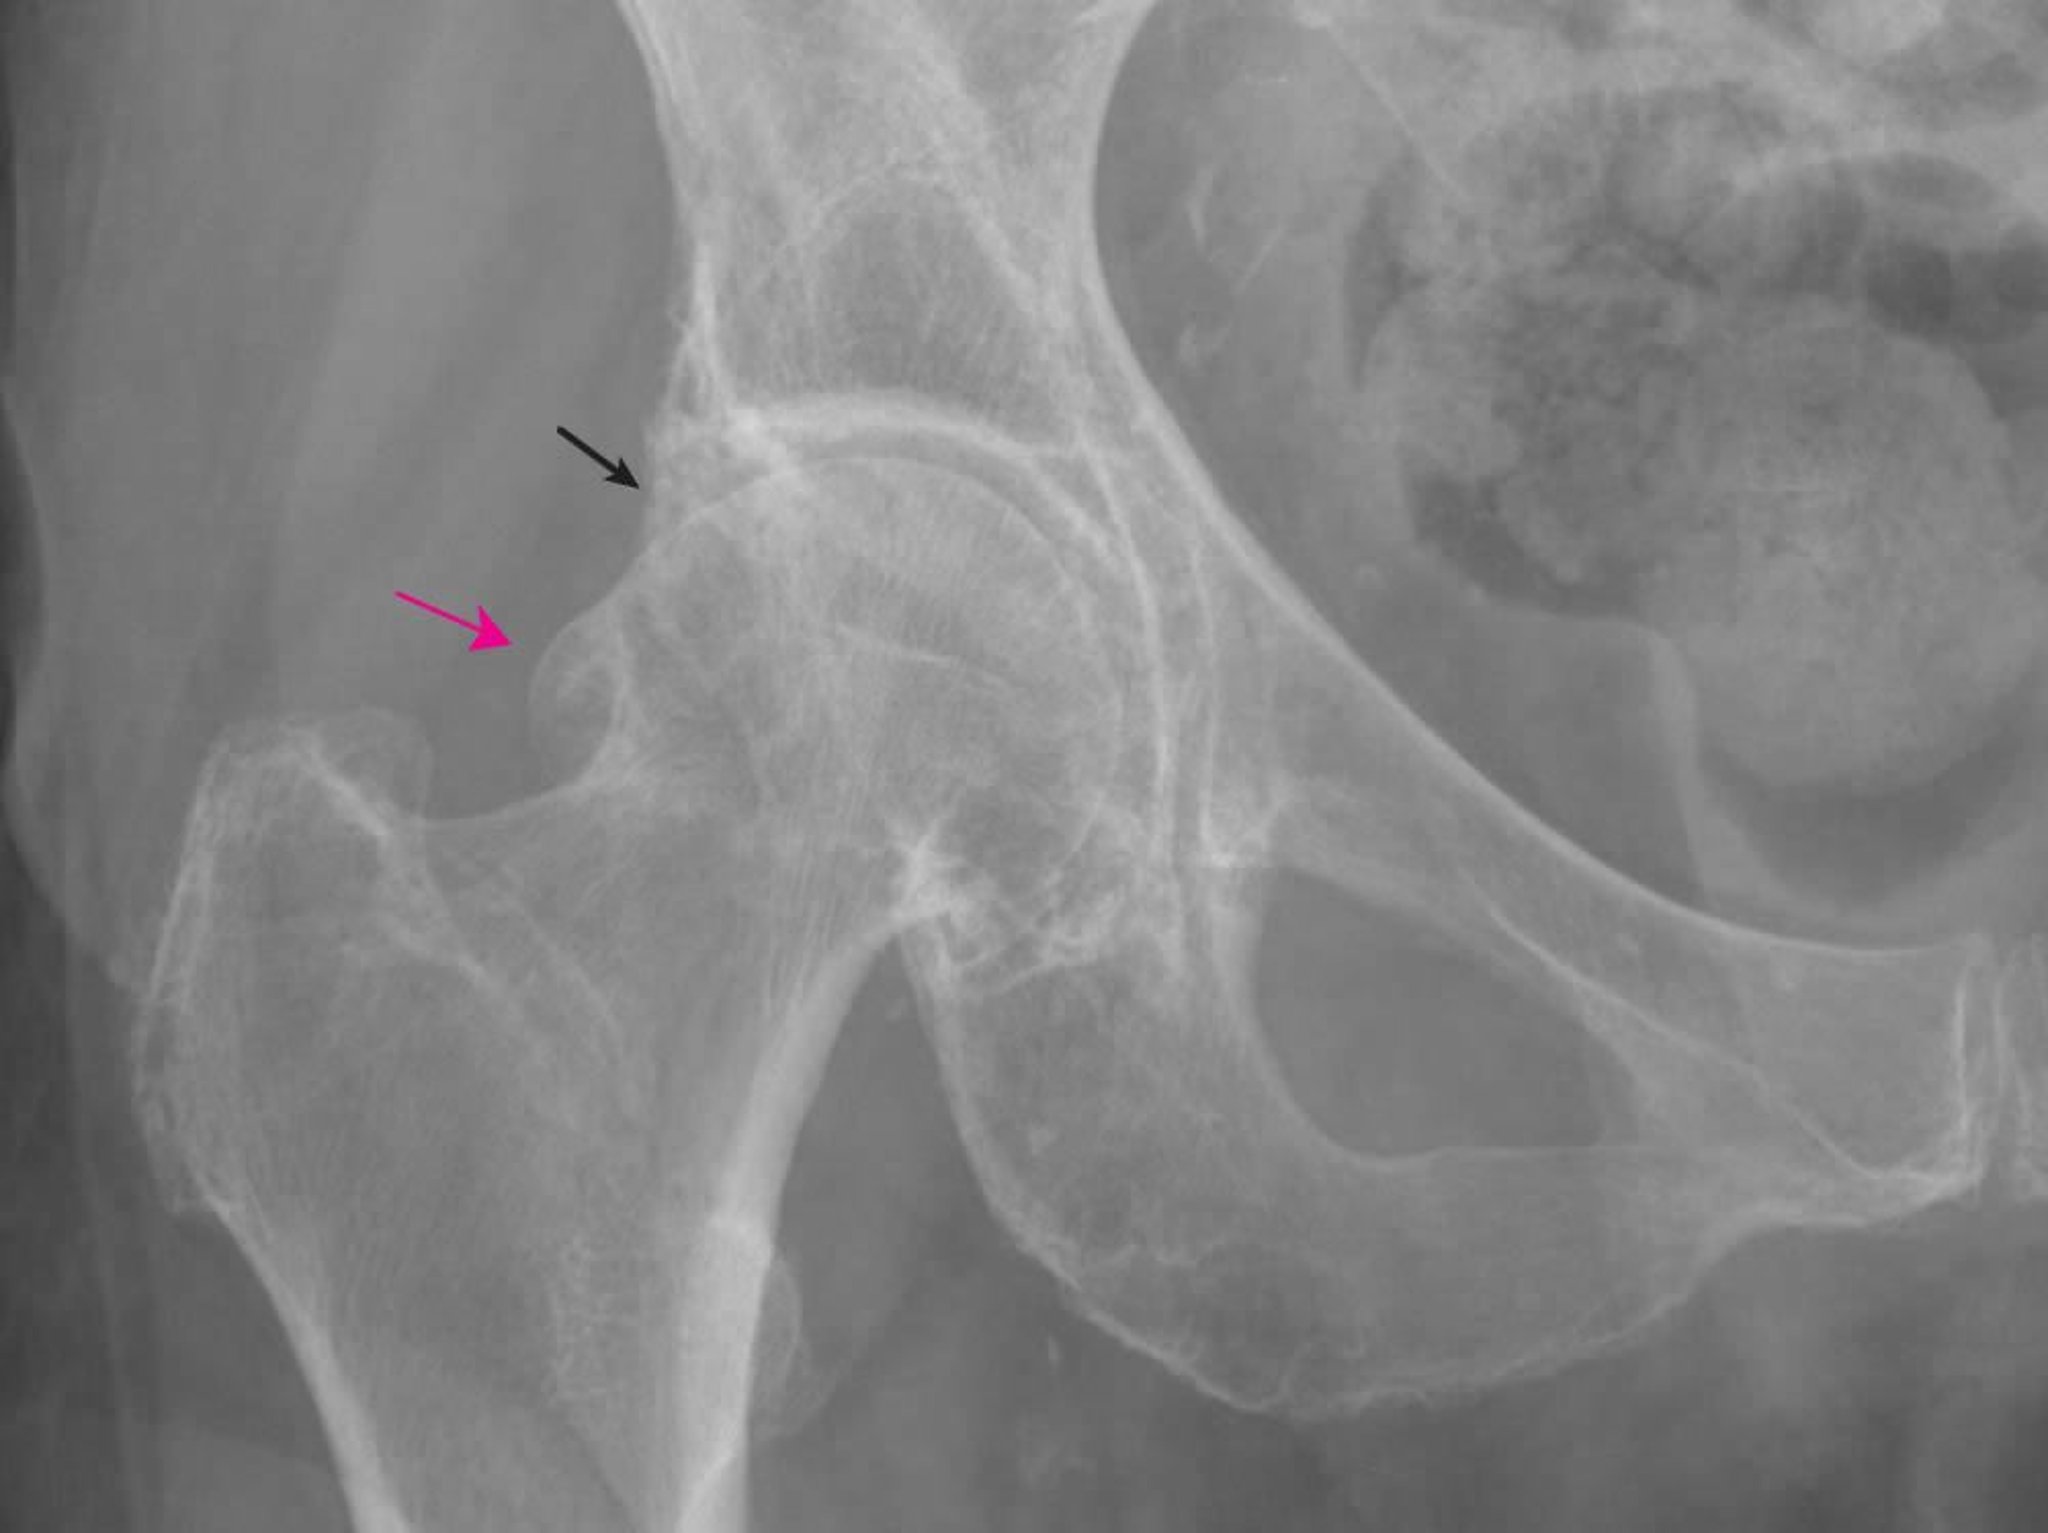

Остеоартроз тазобедренного сустава

Рентгеновские признаки изменений, характерных для остеоартрита, в том числе крупные бедренные (красная стрелка) и вертлужные (черная стрелка) остеофиты и незначительное сужение верхней суставной щели.

Изображение предоставлено Roy Altman, MD.